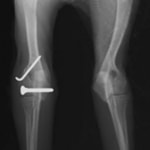

症例3:キルシュナーワイヤーのピンニングによる整復

ペルシャ猫 11ヶ月齢 雄

他院にて左大腿骨遠位の成長板骨折(salter-harrisⅠ型)が認められており、治療相談を目的として来院。当院にて、キルシュナーワイヤーを用いたピンニングにより骨折部位の整復を行いました。術後の経過は良好で、現在も経過観察中です。

術前レントゲン

術後レントゲン

機器

Arthrex社のターゲティングデバイスを用いてピンニングの位置を調整することで、確実な固定を行っています。当院ではこの手術器具以外にも、人の手術にも使用される様々な器具を導入し、手術精度を高め、また医療メーカーと新しい器具の開発、試作にも取り組んでおります。